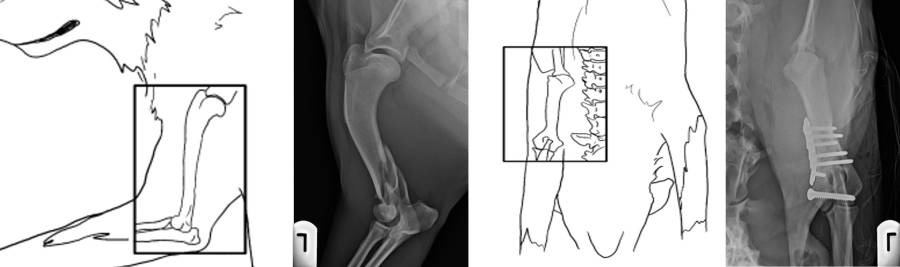

Röntgen Oberarm

Röntgen Hüfte

Röntgen post OP mit Implantaten